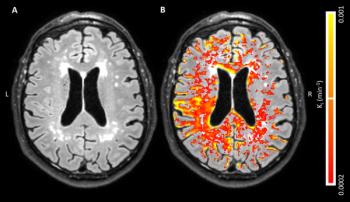

Using MRI to evaluate blood-brain barrier disruption following intracranial hemorrhage may predict severity after intervention.